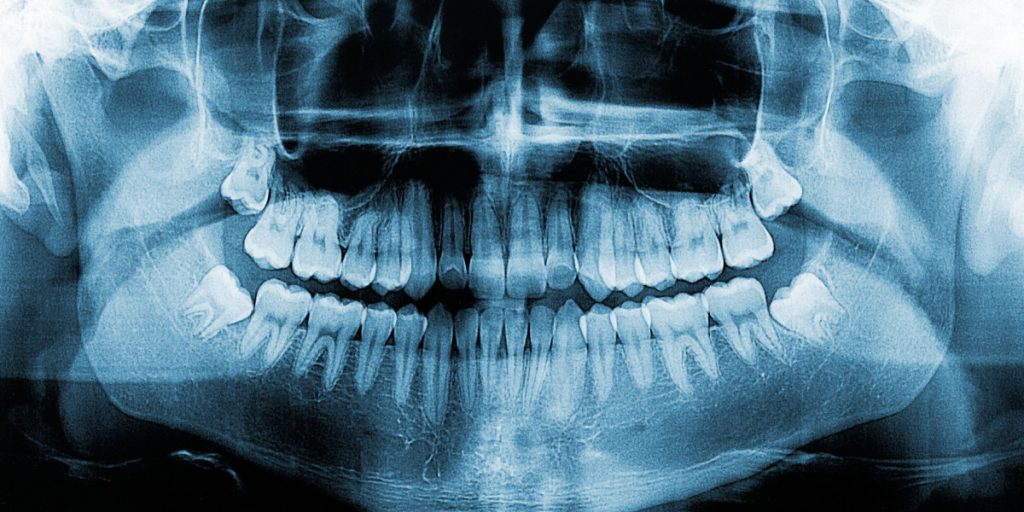

- Radiografía: lesiones típicas con aspecto de “vidrio esmerilado”.